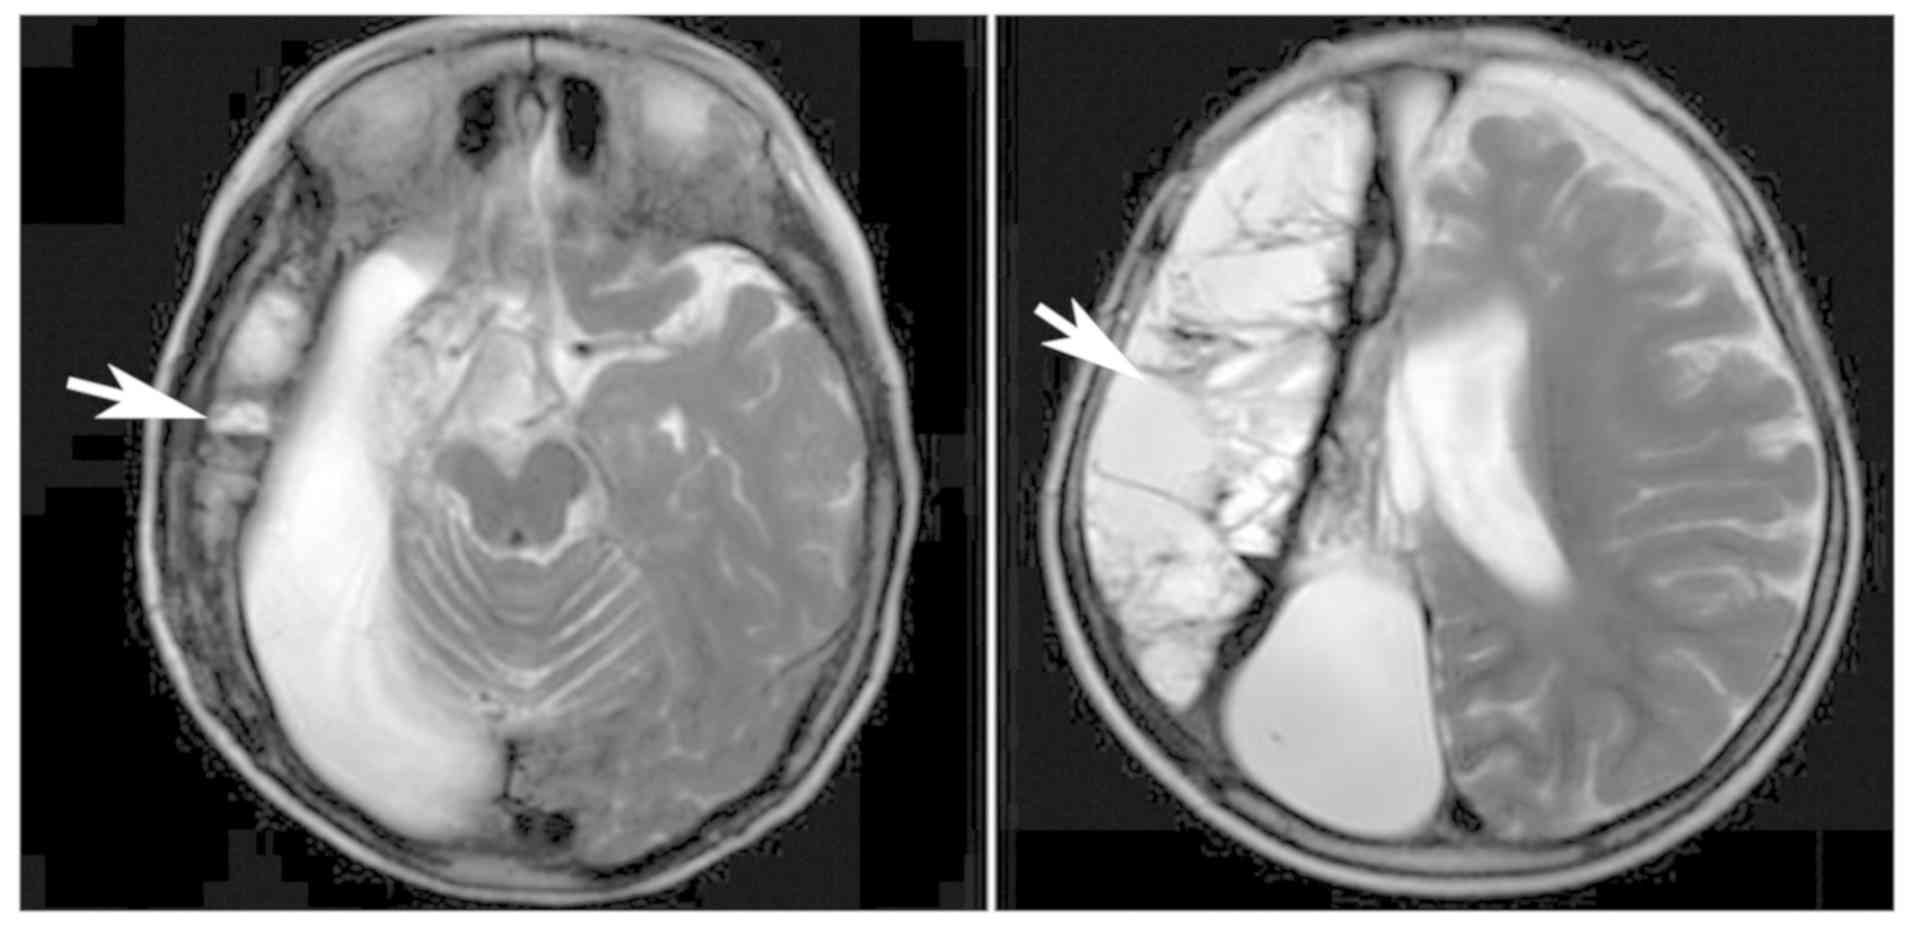

Primary carnitine deficiency in two sisters with intractable epilepsy and reversible metabolic cardiomyopathy: Two case reports

Primary carnitine deficiency (PCD) is a disorder of the carnitine cycle that results in defective fatty acid oxidation. When carnitine cannot be transported into the cells, fatty acid oxidation is impaired, resulting a variety of symptoms, such as chronic muscle weakness, cardiomyopathy, hypoglycemia and liver dysfunction. The clinical manifestations and outcomes of different cases with PCD vary among patients. The present case report focused on two sisters with PCD. The younger sister presented with intractable epilepsy, and the older sister presented with reversible metabolic cardiomyopathy. Potential mutations in the SLC22A5 gene were investigated within the family, and a nonsense mutation [c.760C>T (p.R254X)] was identified in four family members. The two sisters harbored homozygous mutations, whereas their parents presented heterozygous mutations. Metabolic disease screening revealed low plasma free carnitine levels (<5 µmol/l) in the two sisters. The plasma free carnitine levels of their parents were normal, and they were asymptomatic. PCD in the two patients was managed using oral levocarnitine. The metabolic cardiomyopathy of the older sister improved following 3 months of treatment. However, the epilepsy of the younger sister was recurrent with oral antiepileptic therapy lasting one year and eight months, and epilepsy was finally controlled following right cerebral resection. The present case report demonstrated that the clinical manifestations presented by patients with PCD within the same family were different. The results indicated that treatment with levocarnitine supplementation should be initiated as soon as possible before irreversible organ damage occurs. In addition, metabolic decompensation and cardiac muscle functions were improved following carnitine supplementation. The resection of the severely diseased unilateral brain combined with carnitine supplementation and antiepileptic therapy may be an effective treatment for PCD with intractable epilepsy complications.